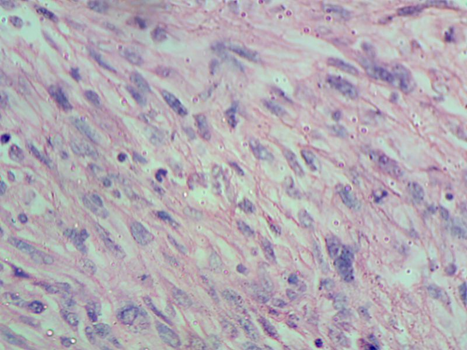

A 21 year old male patient reported to the department of Oral Medicine and Radiology with the chief complaint of swelling on left side of face for past three months (Figure 1). He initially noticed a small nodular growth on left cheek region which has increased to the present size. On clinical examination a solitary innocuous, lobulated, sessile, painless and non-hemorrhagic mass with soft consistency was protruding from the left side of mouth. The growth was associated with restricted mouth opening, difficulty in speaking and mastication (Figure 2). Examination of lymph nodes revealed ipsilateral submandibular lymph nodes were enlarged, non tender and fixed to underlying tissue. Patient gave the history of consumption of 10-15 packets of gutkha for past 7-8 years, bidi smoking (1-2 packets of bidi per day) and occasional consumption of alcohol. On the basis of the patient’s history and clinical examination a preliminary/tentative diagnosis of malignancy involving the left buccal mucosa was considered. Standard radiological and haematological (Figure 3) examinations were performed, but no noteworthy results were found. Later, incisional biopsy was done under local anesthesia and histopathological findings revealed parakeratinized stratified squamous epithelium which appeared normal in architecture with hyalinized connective tissue stroma. Beneath the hyalinized stroma, the tumor mass showed proliferating cells arranged in interlacing fascicles. High power view showed plump and proliferating spindle cells arranged in interlacing fascicles giving a herring bone pattern. The tumor cells were pleomorphic with hyperchromatic nucleus and a few cells had vesiculated nucleus with multiple nucleoli. It was determined by these results that the condition was moderately differentiated fibrosarcoma (Figure 4,5&6).

Figure 5. H&E section (100X) showing spindle cells arranged in Herring bone pattern.

Figure 6. H&E section (1000X) showing pleomorphic spindle cells.

A herringbone pattern is typically formed by fascicles of spindle-shaped cells in histopathologically well-differentiated fibrosarcomas. In comparison to well-differentiated tumours, poorly differentiated tumours have less organised cells that can have an oval or rounded shape, minor pleomorphism, increased mitotic activity, and a tendency to make less collagen [6]. The differential diagnosis of fibrosarcomas may include spindle cell tumours, and an appropriate diagnosis may only be made by immunohistochemical analysis and meticulous study of several sections and specific stains [1]. The preferred course of treatment for fibrosarcoma is radical surgery. Chemotherapy and radiotherapy might be used as palliative care or in cases that are not treatable. Tumour size, histology grade, and appropriate surgical therapy with no side effects all directly affect prognosis [2,3,9].